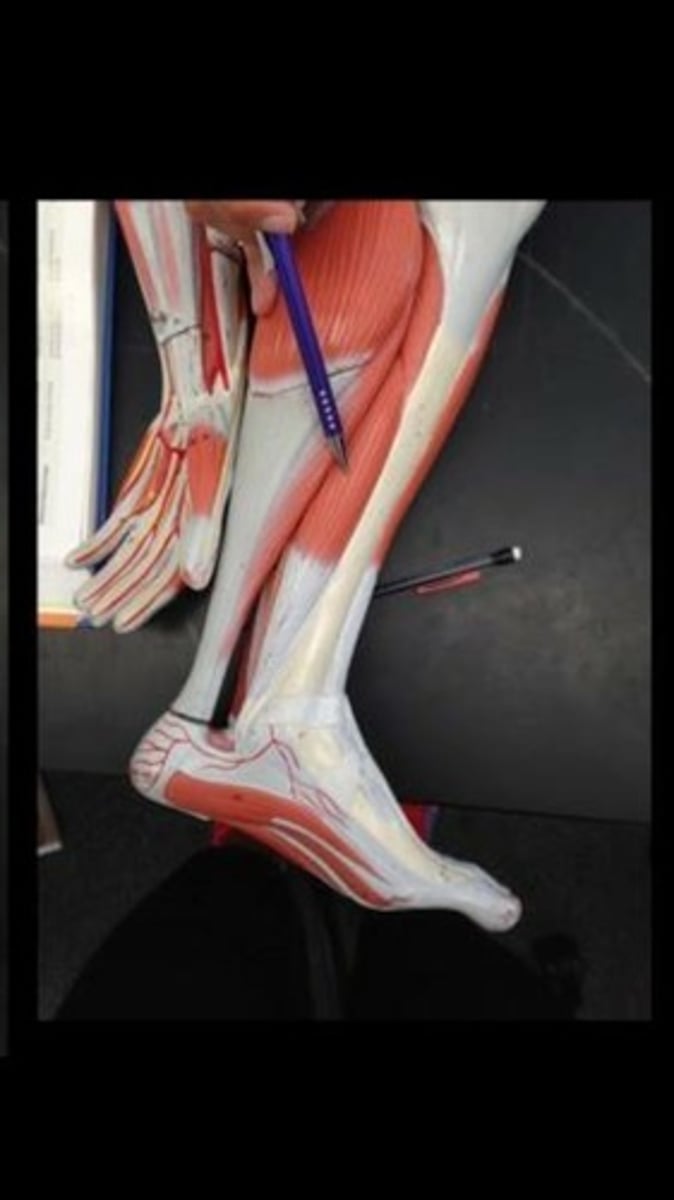

Gastrocnemius lateral head

Gastrocnemius medial head

Soleus